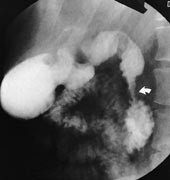

ERCP kan også gi et typisk bilde, idet pancreasgangen i annulus kan fremstilles. Den har et karakteristisk sirkelformet forløp rundt duodenum (2) og munner ut i pancreas’ hovedgang nær papillen. ERCP kan i dag ikke anbefales som første metodevalg ved mistanke om annulær pancreas, da undersøkelsen i seg selv kan fremprovosere pankreatitt. Annulær pancreas kan være kombinert med den hyppigere forekommende varianten pancreas divisum (8). Gangen fra den annulære del av pancreas vil da munne ut sammen med den separate gangen for ventrale pancreasanlegg. Annulusgangen kan også ha separat munning i duodenum og da være vanskelig eller umulig å kanylere. Uttalt duodenal obstruksjon kan vanskeliggjøre ERCP-undersøkelsen.